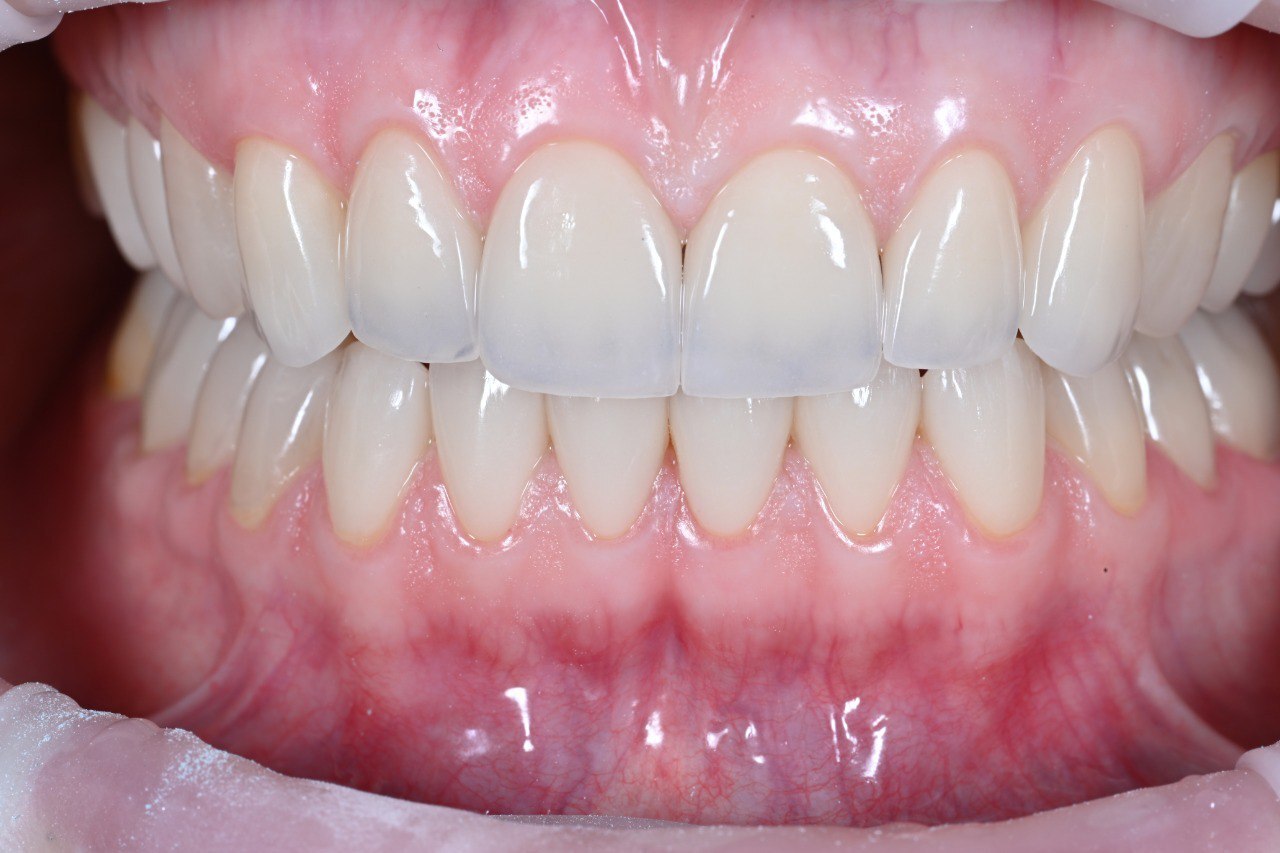

Константин Олегович Юшков

Планирование от результата. Выбор количества опор и материала постоянной конструкции. Работа с мягкими тканями на этапе провизорных.

До

После